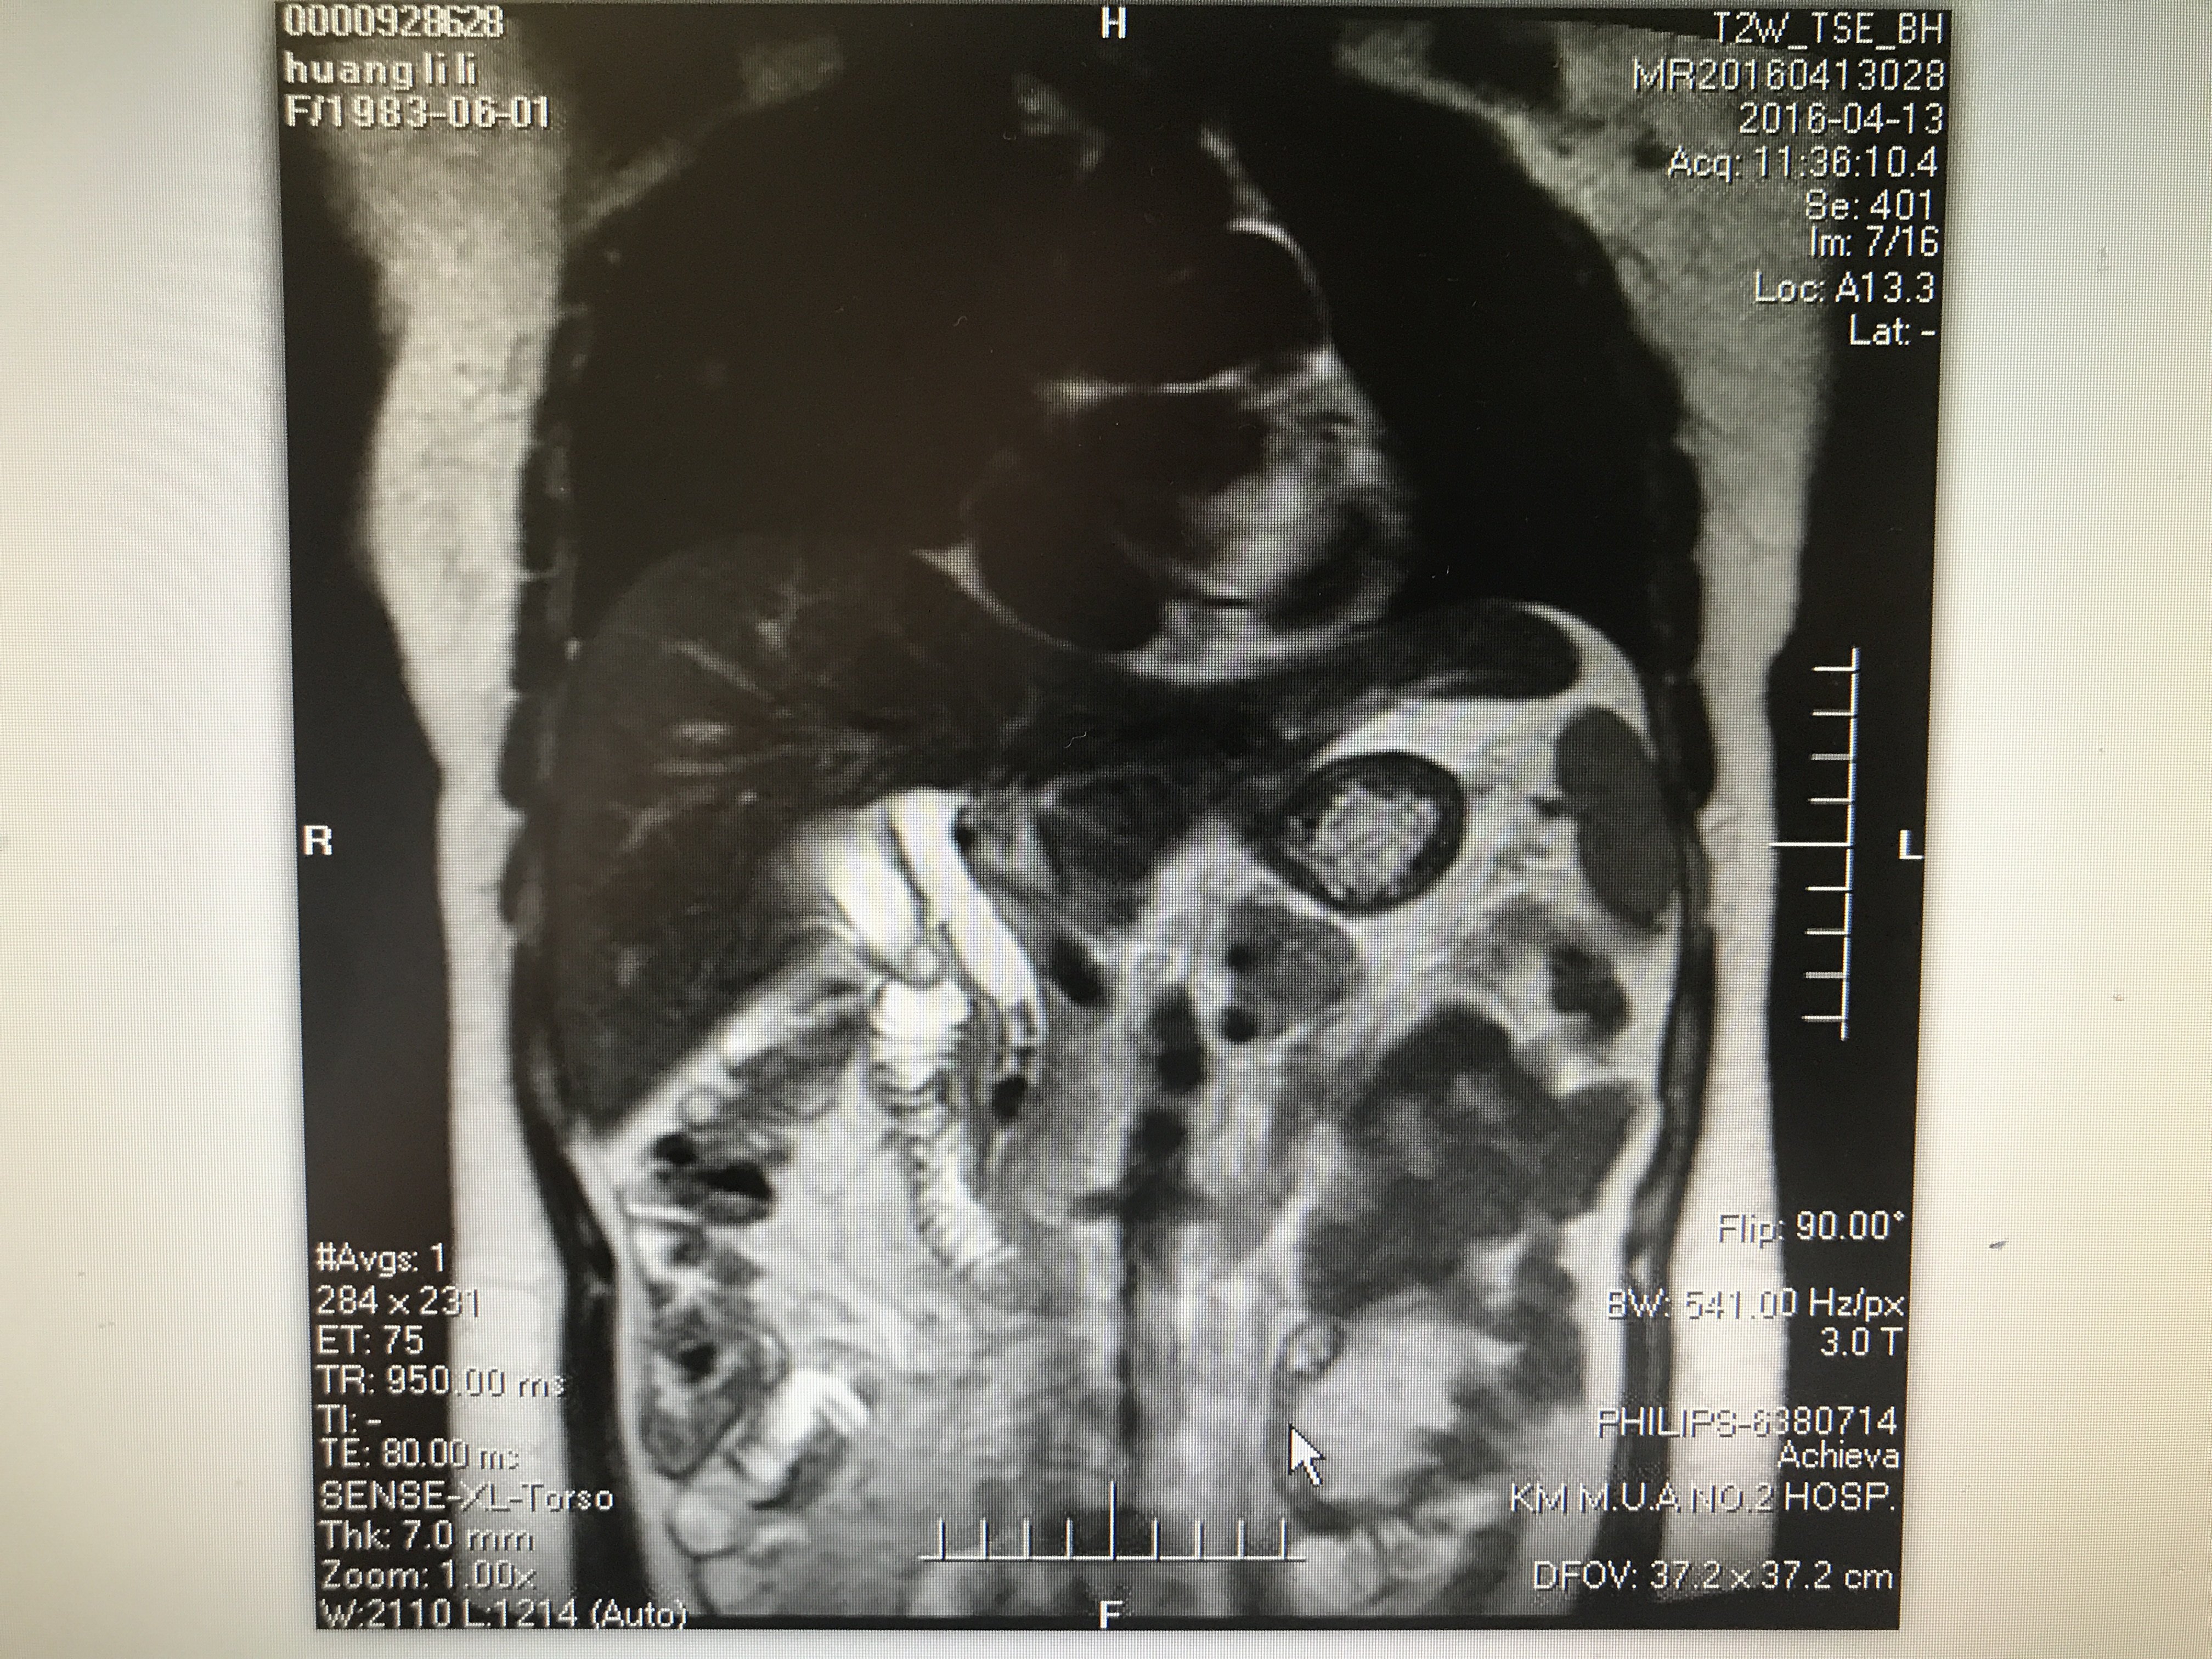

这里主要指的是CT、核磁共振等特殊检查的片子。

首先要解释的是一个是您拿到的影像片子,另一个是您拿到的报告单。

①报告单是放射科医生做出检查后给出的提示是总体性的且有一定法律效应的结论。

②我们专科医师看片子需要根据专科的角度去判断片子中疾患的部位、大小、血液供应、周围粘连、目前疾患的进展、甚至手术方案、病情的预后都已经了然在心中了。

所以完整的把检查资料传到医生的手中是非常关键的。

如何正确的把拍的片子发给医生看!

一般的报告就不再说了,正常拍摄就可以,我说的是片子应该怎么拍,一般是1-4小张拍一次,如下图: